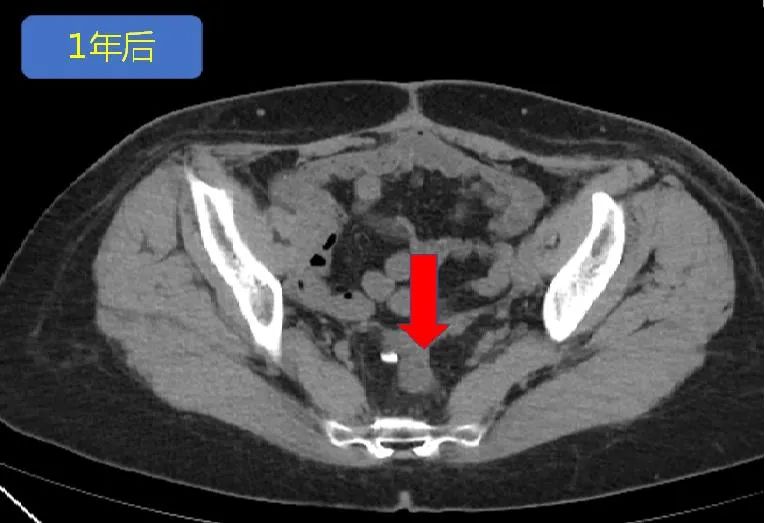

△PD-1抗体治疗1年后,肿瘤几乎完全消失

乘胜追击,肿瘤完全消失。

在后续治疗中,张女士的肿瘤继续缩小。PD-1抗体治疗1年后,肿瘤几乎完全消失,疗效达到完全缓解(图3所示)。2020年6月,在PD-1抗体治疗满两年后,张女士结束了所有治疗。